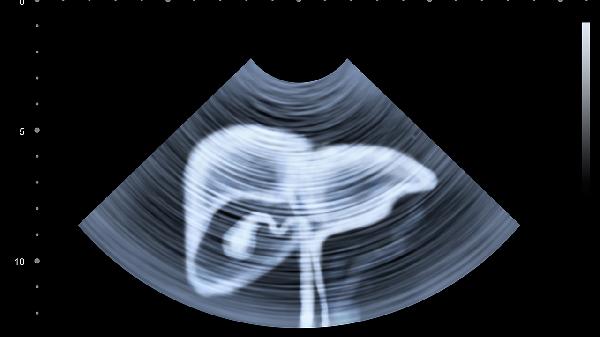

出现上述任何一个症状,都要尽快做肝功能、乙肝病毒DNA、甲胎蛋白和肝脏B超检查。

即使没有症状,乙肝患者也应该每3-6个月复查一次肝功能,每年做一次肝脏超声检查。